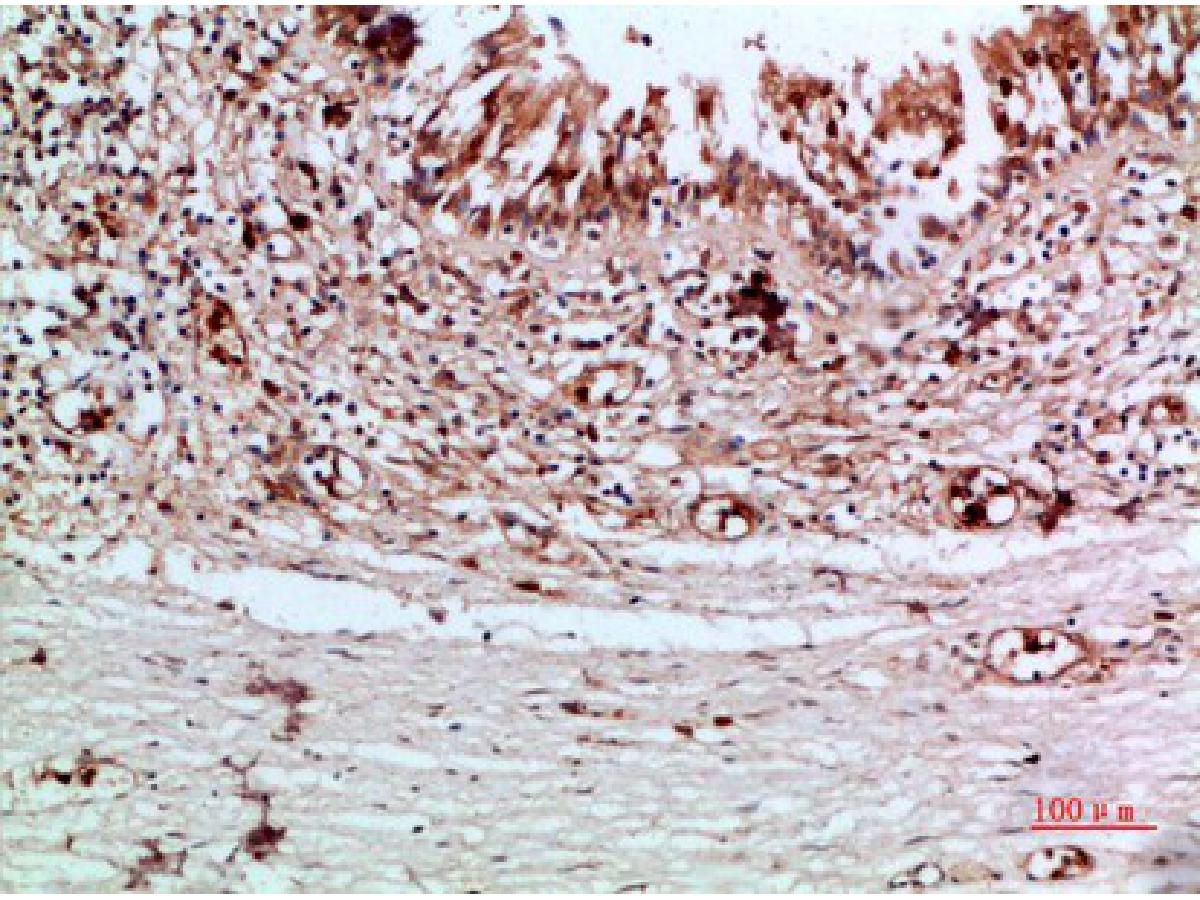

Thyroglobulin Recombinant Rabbit Monoclonal Antibody [JE47-61]

IHC-P